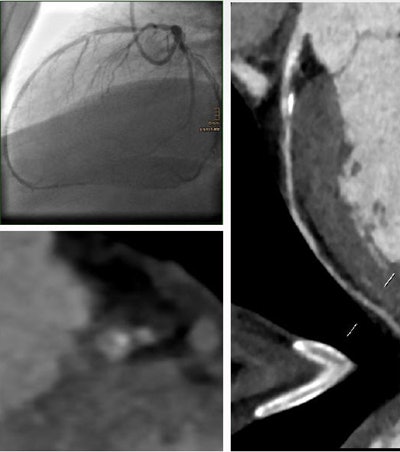

A 62-year-old smoker with hypertension, dyslipidemia, and diabetes had a 93% stenosis in the left anterior descending artery. The MLA was 1.4 mm2, the minimum lumen diameter was 1.1 mm, the area stenosis was 75%, and the diameter stenosis was 69%. The patient was revascularized. All images courtesy of Dr. Fabian Plank.Visual grading has limitations

"Therefore, we evaluated secondary measurements in CTA for the assessment of hemodynamic relevance and compared them to invasive angiography as our reference point," he said. The imaging was followed by coronary revascularization.